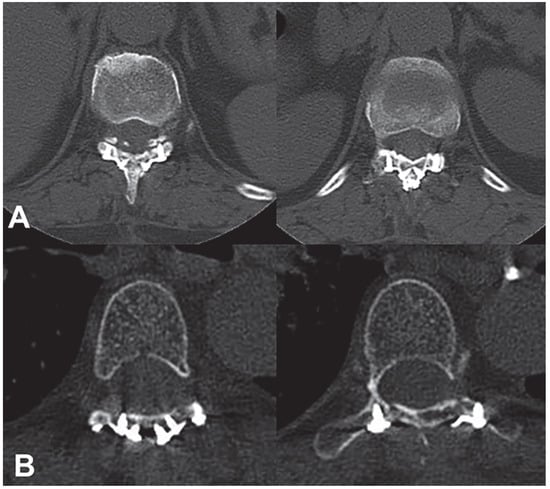

3.5. Results of the Biomechanical Experiments

| FE | 14.41 ± 1.19 | 12.94 ± 0.67 | 2.93 ± 0.24 |

| LB | 17.26 ± 1.09 | 13.10 ± 0.54 | 3.12 ± 0.24 |

| AR | 13.19 ± 1.22 | 11.11 ± 0.41 | 5.82 ± 0.38 |